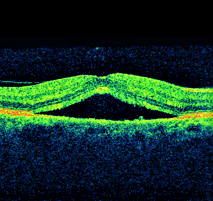

1a.Central serous retinopathy

1b.Central serous retinopathy.